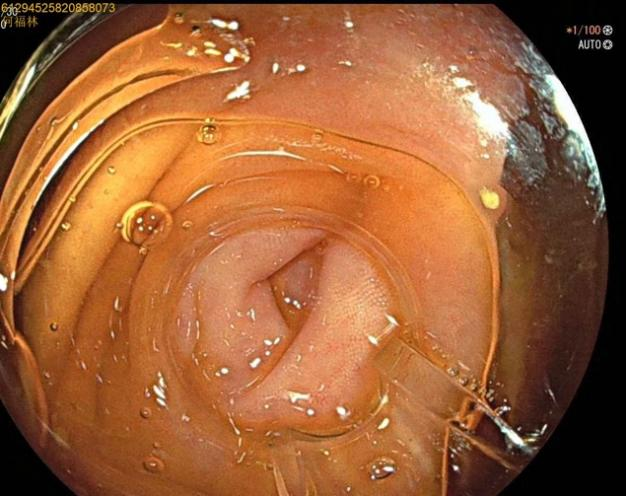

52岁,女性患者,主因“反复右下腹痛1年,再发2天”入院,既往有急性阑尾炎发作病史,入院腹部查体:右下腹麦氏点明显压痛,无肌紧张及反跳痛;完善腹部+盆腔CT示:阑尾管腔增粗并阑尾粪石形成,周围多发淋巴结显示。结合患者的病史及检查考虑慢性阑尾炎急性发作。次日,行肠镜检查,进至阑尾口,置入子镜(洞察内镜)进入阑尾,见阑尾黏膜充血、水肿,附着有白色絮状分泌物,确诊急性阑尾炎发作,进一步行内镜下逆行性阑尾治疗术,术中给予阑尾腔冲洗后植入塑料支架,术后患者腹痛即可缓解。